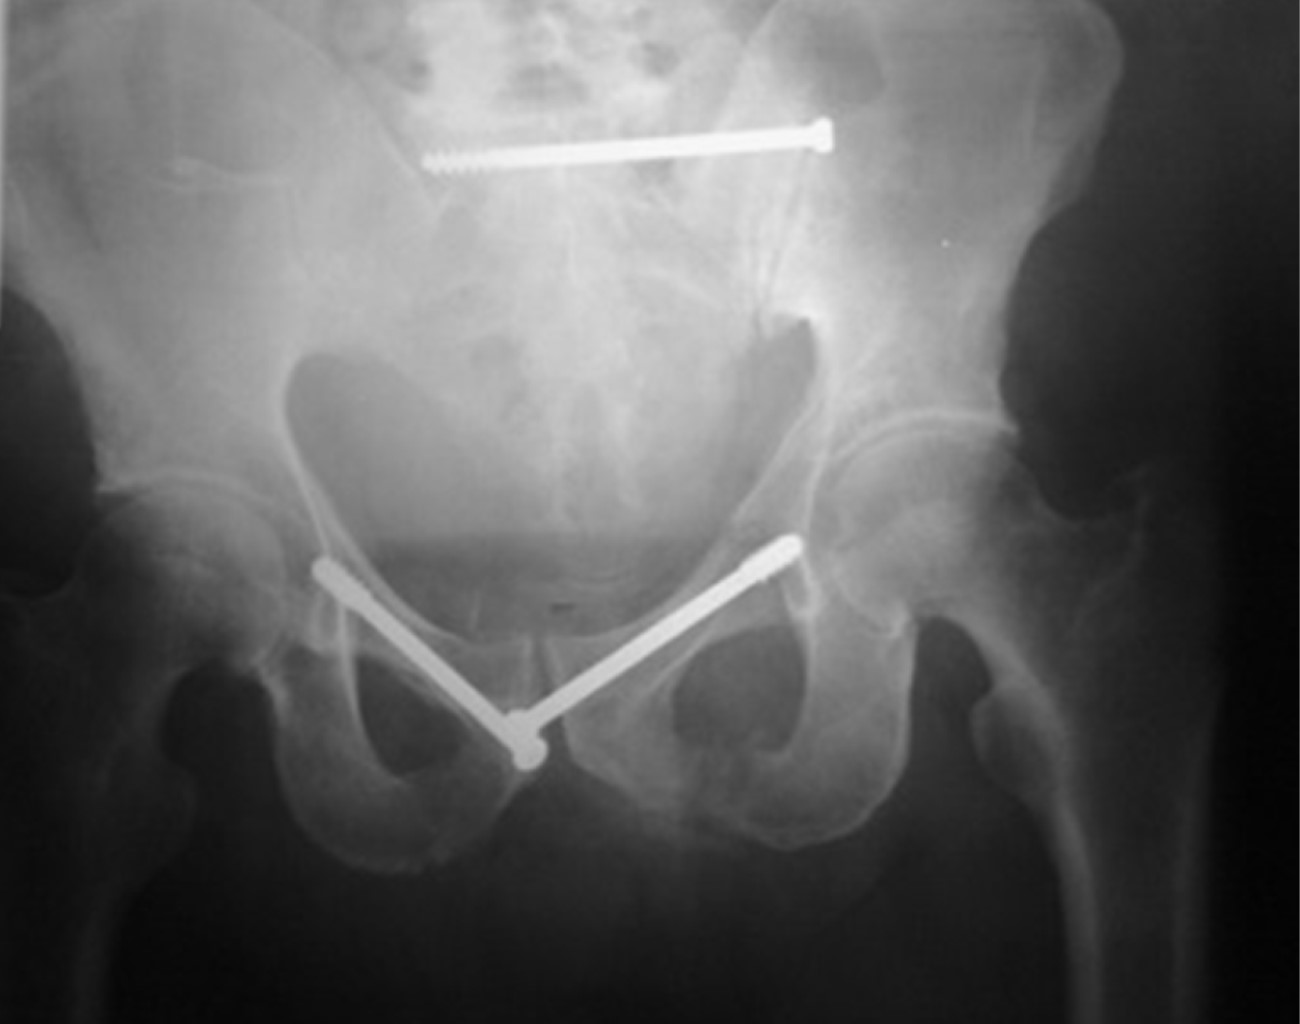

La osteosíntesis percutánea de la pelvis y acetábulo engloba un conjunto de técnicas de sujeción ósea mediante abordajes mínimamente invasivos, introduciendo implantes pequeños, tornillos canulados, a través de incisiones de menos de 1 cm. Dentro de la variedad de fijación percutánea es posible encontrar: tornillos iliosacros, tornillos en la columna anterior de acetábulo (anterógrado y retrogrado), en la columna posterior del acetábulo (tornillo ilioisquiático), tornillo mágico (magic screw) y tornillo a las ramas iliopúbicas (retrógrado)(Figura 1).1

Figura 1